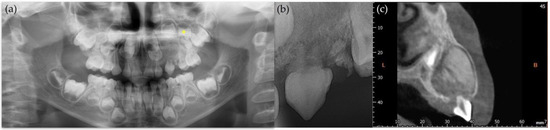

2. Case Report